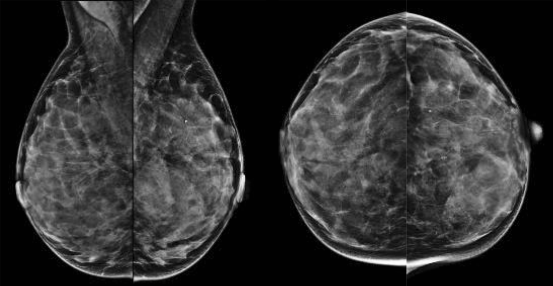

Figuur 1

Standaardmammogram, MLO-opnamen en CC-opnamen van dense mammae.